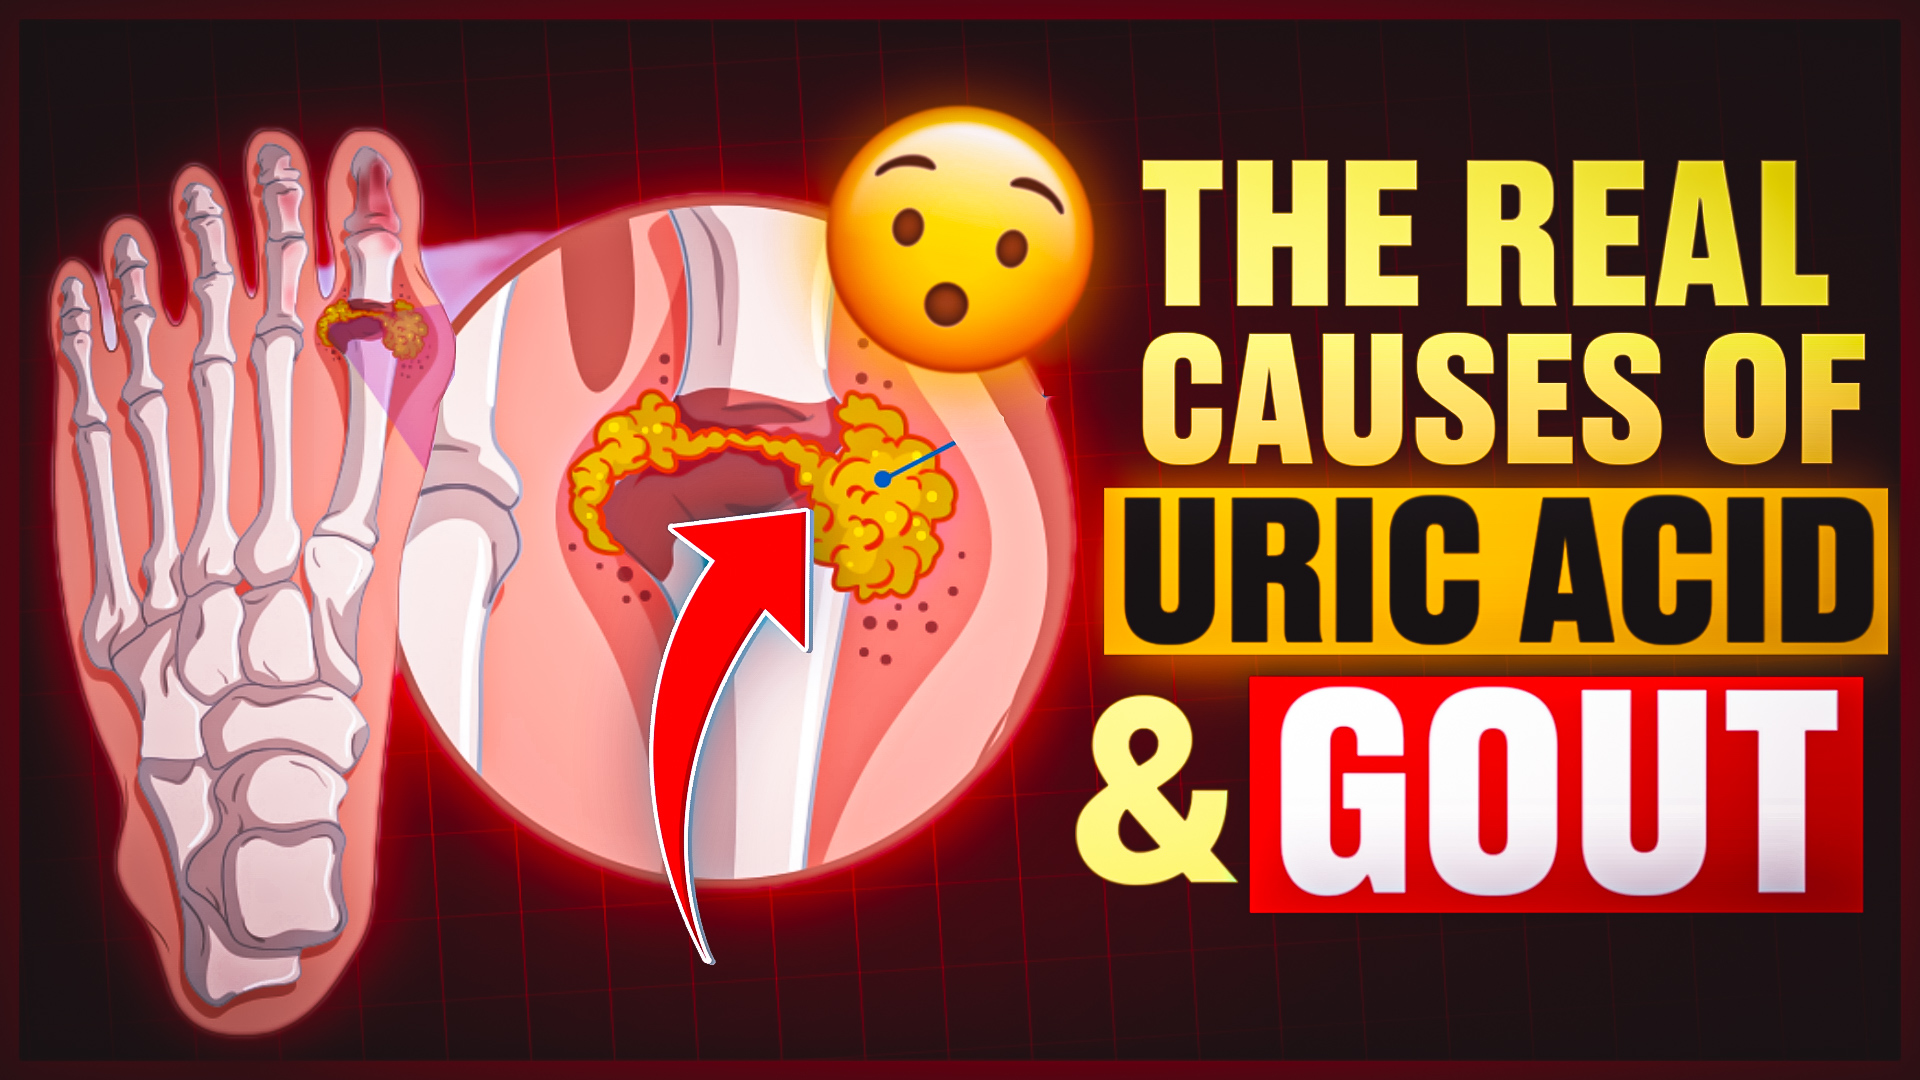

Diseases & Conditions

Bone, Muscle & Pain Related Disorders